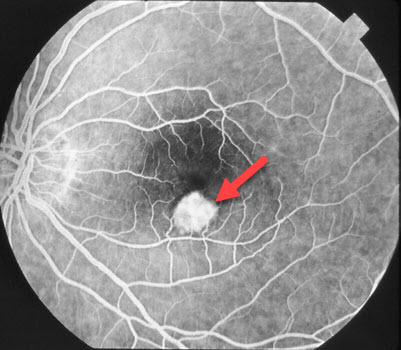

The most important step in accurately diagnosing the ocular histoplasmosis syndrome consists of a careful eye examination by an eye doctor familiar with all aspects of this disease. During the examination, your doctor will dilate your pupils and look for histoplasmosis scarring, leakage, and bleeding. Your doctor may need to perform an OCT scan or fluorescein angiography to better evaluate the histoplasmosis scars.

The histoplasmosis fungus, which is present in soil throughout the Mississippi and Ohio River Valley regions, is inhaled early in life and causes a usually asymptomatic and self-limited infection throughout the body, including the lungs and choroid (the vascular layer lining the retina). For unknown reasons, several decades after the initial infection, the choroidal scars may develop abnormal blood vessels (macular neovascularization, MNV) which leak fluid and blood. This leakage can only be seen on a careful, dilated eye examination since the eye looks normal from the outside. Distorted central vision and loss of reading vision occur when the leakage involves the macula, that part of the retina we use for our straight-ahead reading vision. There are many causes of MNV including angioid streaks, choroidal rupture, degenerative myopia, idiopathic, and age-related macular degeneration.